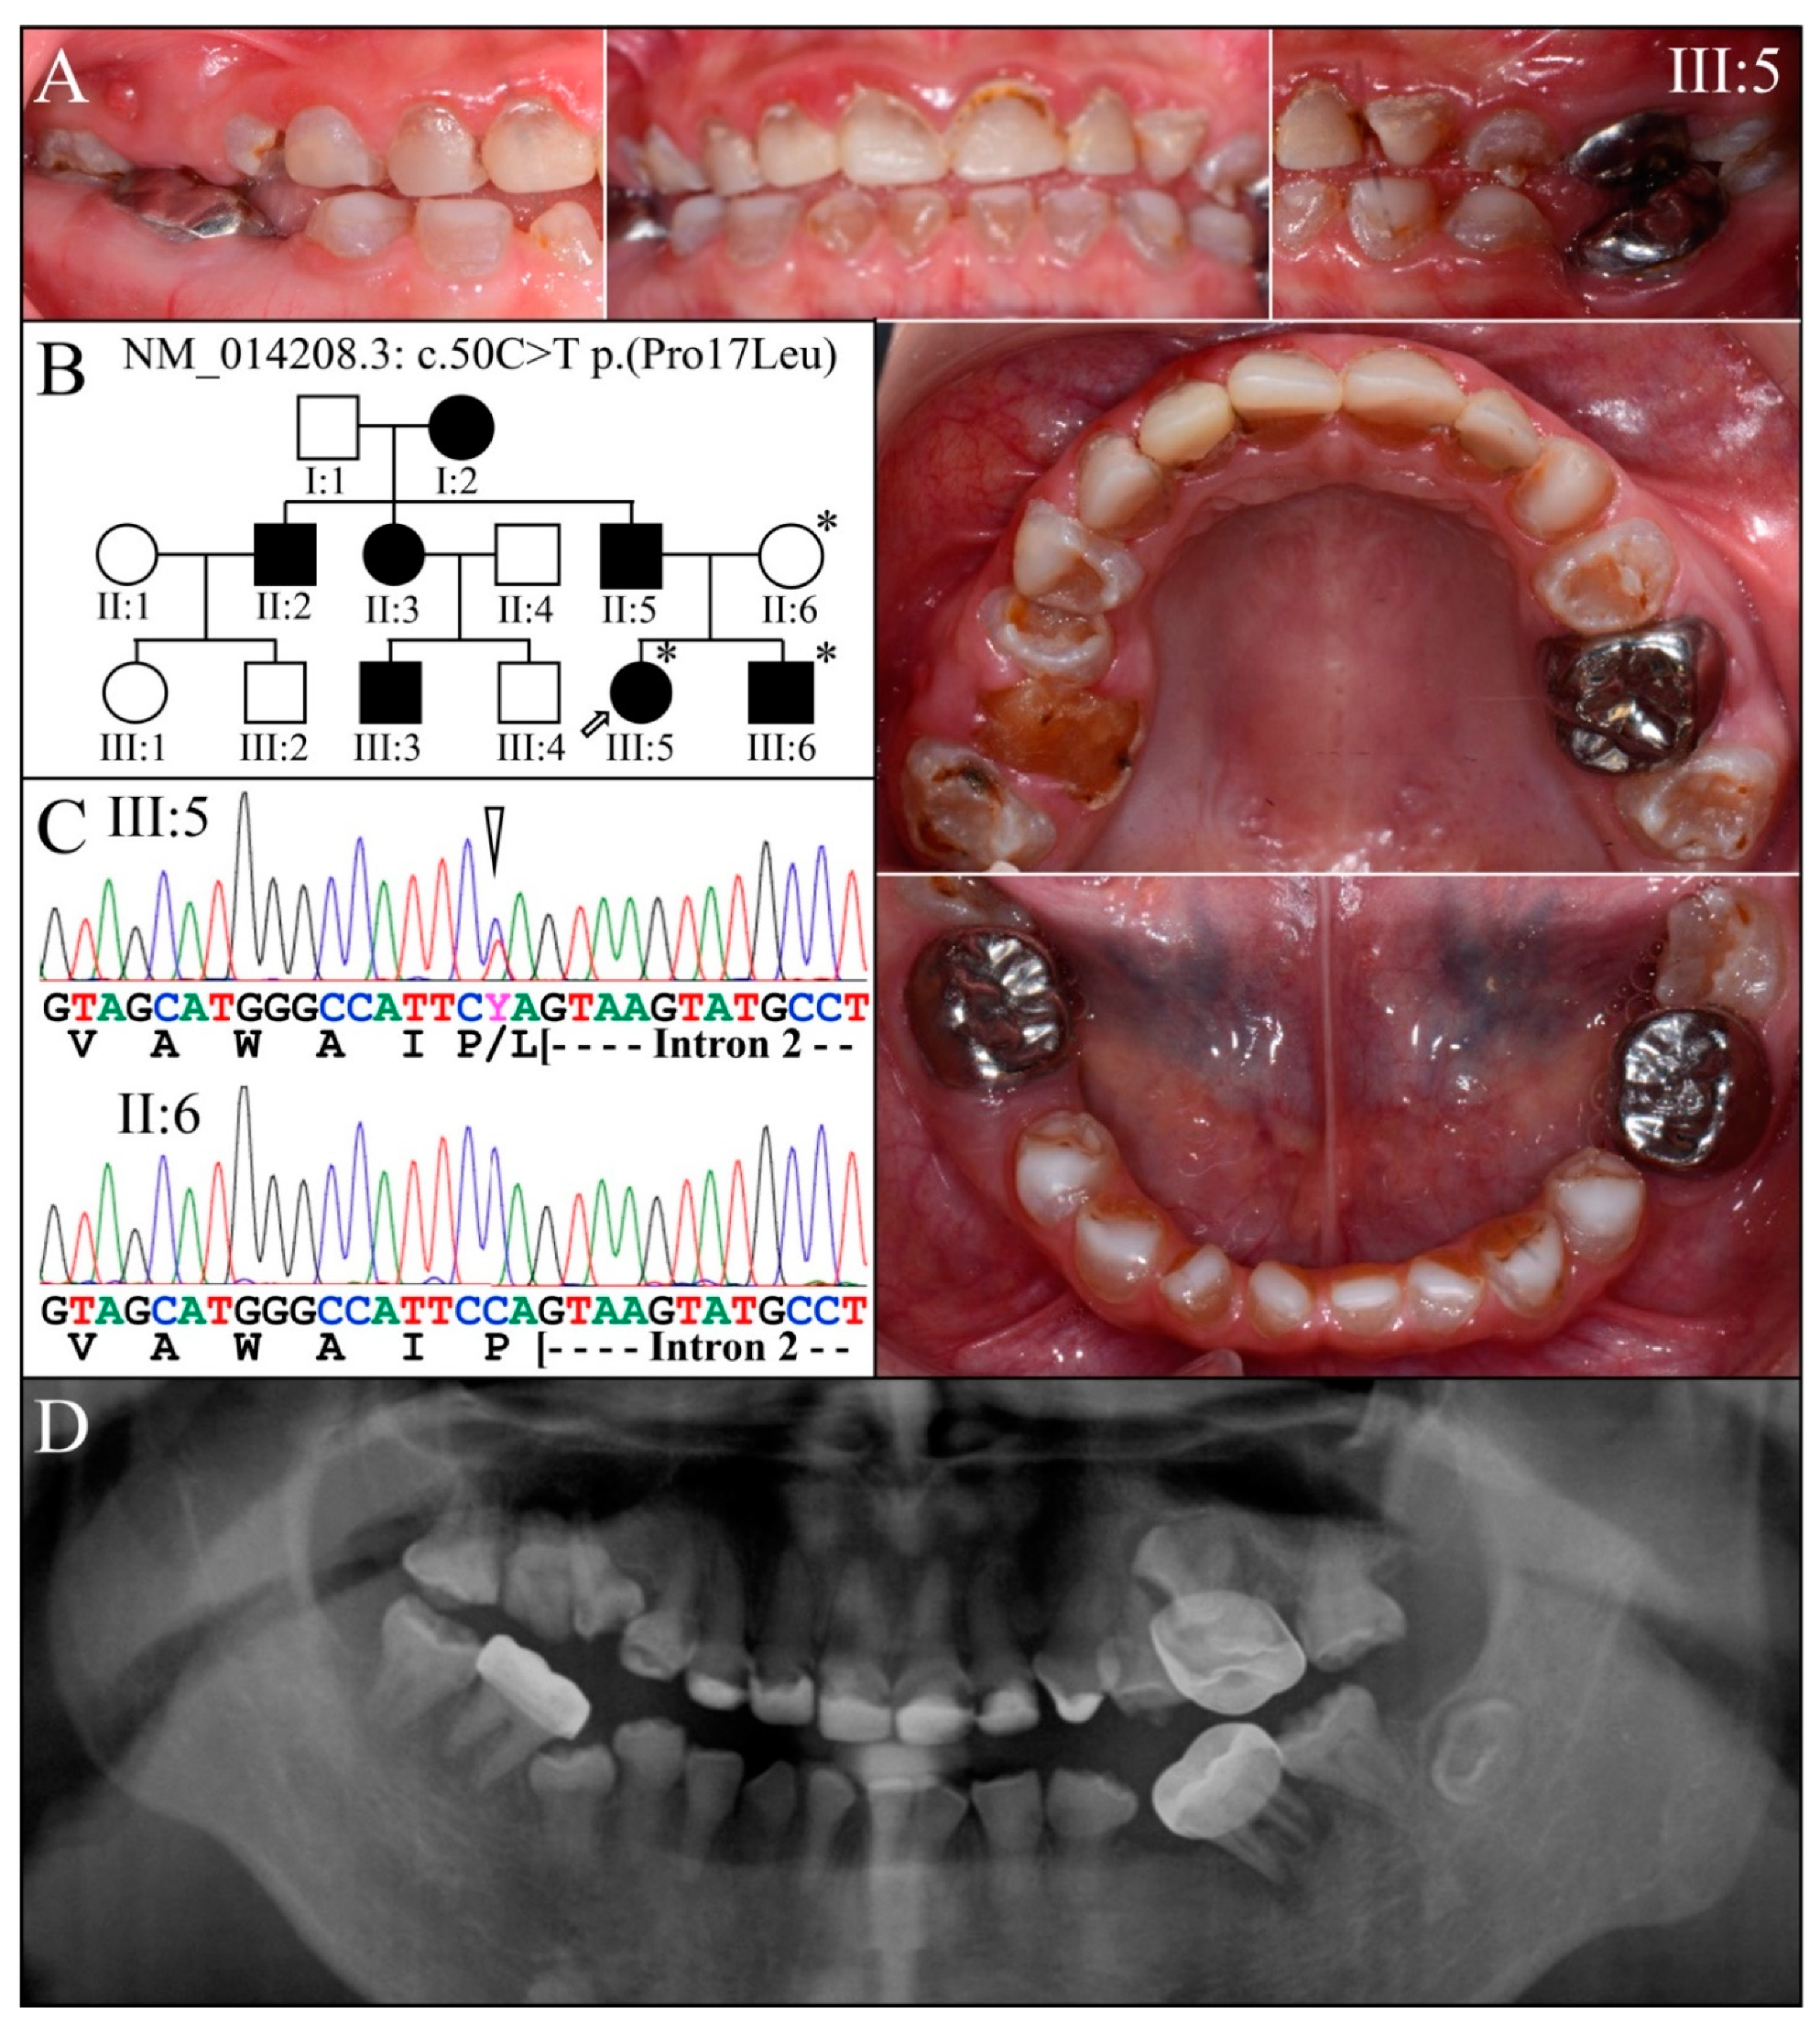

3.2. Four Families with DGI-III: 5′ DSPP Mutations

| 5 | Exon 2 | g.7430C>T | c.50C>T | p.(Pro17Leu) | Family 1, [61,62,63] |

| 1 | Illumina HiSeq 2500 (WES) | NG_011595.1:g.7430C>T; NM_014208.3:c.50C>T; NP_055023.2:p.(Pro17Leu) | Missense | II:6, unaffected mother: 136.75× III:5, affected 1st child: 159.3× III:6, affected 2nd child: 129.86× |